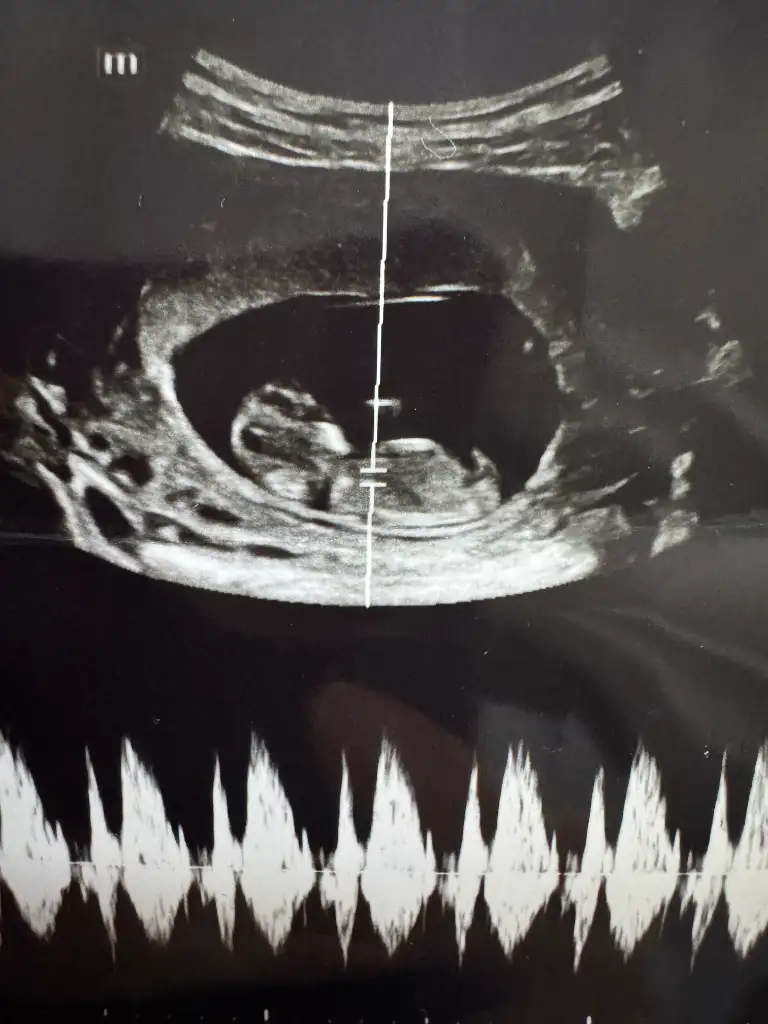

8+6 karından ultrasonla çekildi cinsiyet tahmini yapabilecek var mı acaba

Eklentiler

• IMG_20250616_223900.webp

IMG_20250616_223900.webp

11,8 KB · Görüntüleme: 62